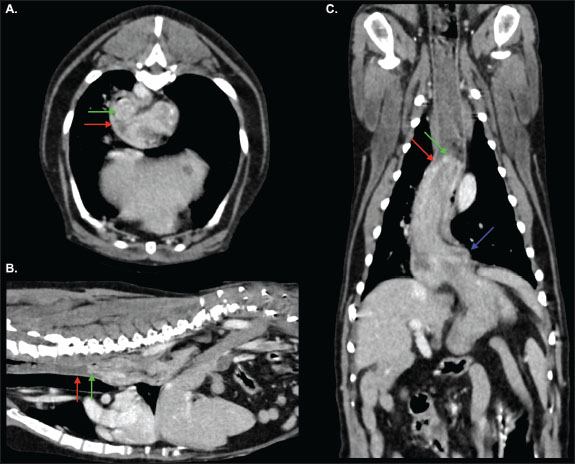

Pre-contrast acquisitions demonstrated a normally positioned stomach; however, the gastric fundus was cranially herniated through the oesophageal hiatus into the caudal esophageal lumen on the venous-phase post-contrast scan (Figs. 1 and 2). The distal oesophageal wall encircled part of the gastric fundus, creating a target-like appearance on transverse-plane images (Fig. 3). The orad oesophagus contained a small-to-moderate amount of heterogeneous fluid-to-soft-tissue-attenuating material. Delayed post-contrast images showed the stomach had returned to its normal anatomical position.

Fig. 3. Transverse-plane images of the thorax from the venous-phase acquisition at approximately the level of the T4 (A), T5 (B), T8 (C), T9 (D), and T10 (E) vertebrae. The gastric fundus (green arrow) has herniated cranially through the oesophageal hiatus into the caudal thoracic oesophagus (red arrow). Note that unlike in cases of hiatal herniation, the distal oesophageal walls are visualised surrounding part of the gastric fundus, creating a target-like appearance, indicative of intussusception.